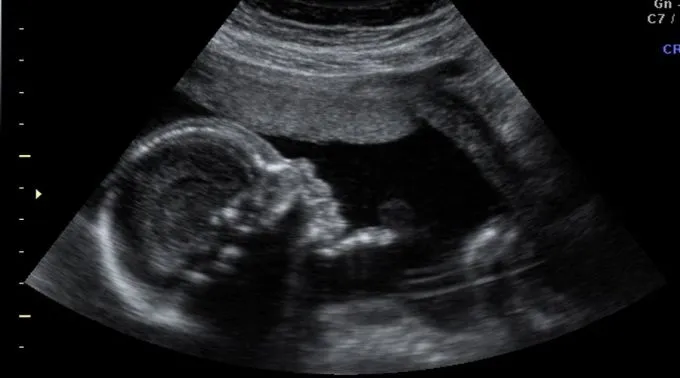

Ultrassonografia / Flickr de Maddalena (CC-BY-NC-SA-2.0)